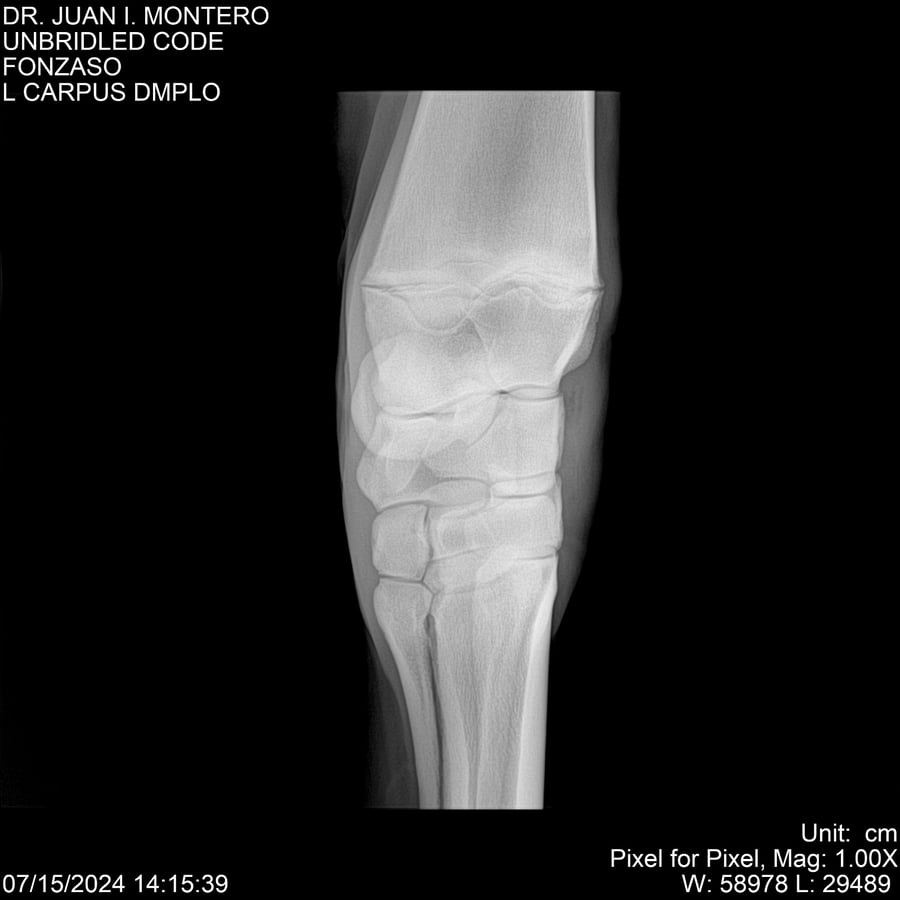

• Empresa: Abelenda N. R., Walter Hugo